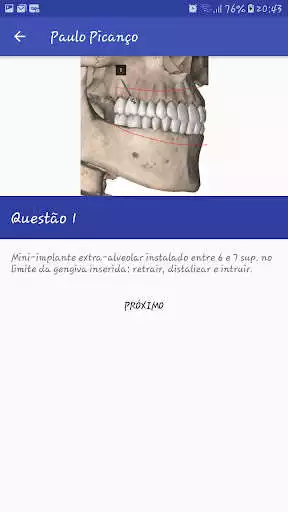

Com este aplicativo o ortodontista poderá optar por uma das localizações ou a combinação de mini implantes visando otimizar o tempo e os resultados do tratamento ortodonticoUpdates: